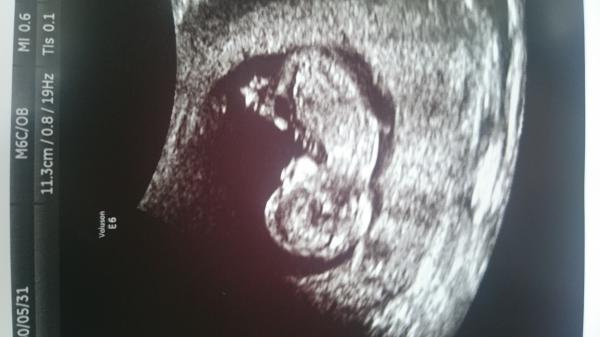

Tänkte att jag startar en tråd för oss som är beräknade i maj. Jag är beräknad till 1 maj med andra barnet. Storebror är född 15 april 2014 så det blir lite över två år mellan ettan och tvåan om allt går som det ska. :)